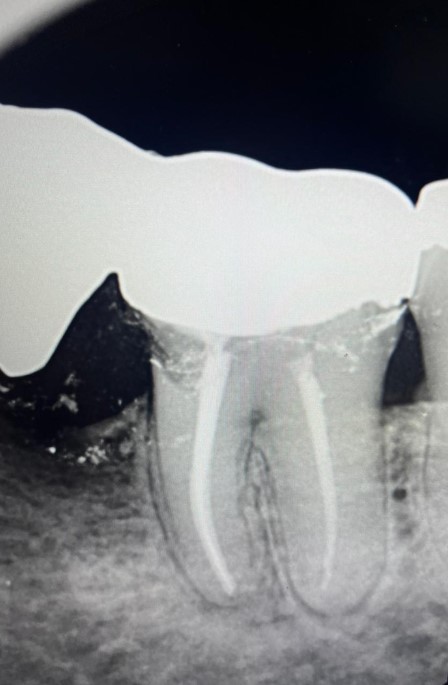

Casos Clínicos

Excelência comprovada em imagens radiográficas.

INICIAL

Diagnóstico Inicial

FINAL

Tratamento Concluído

Detalhes Radiográficos